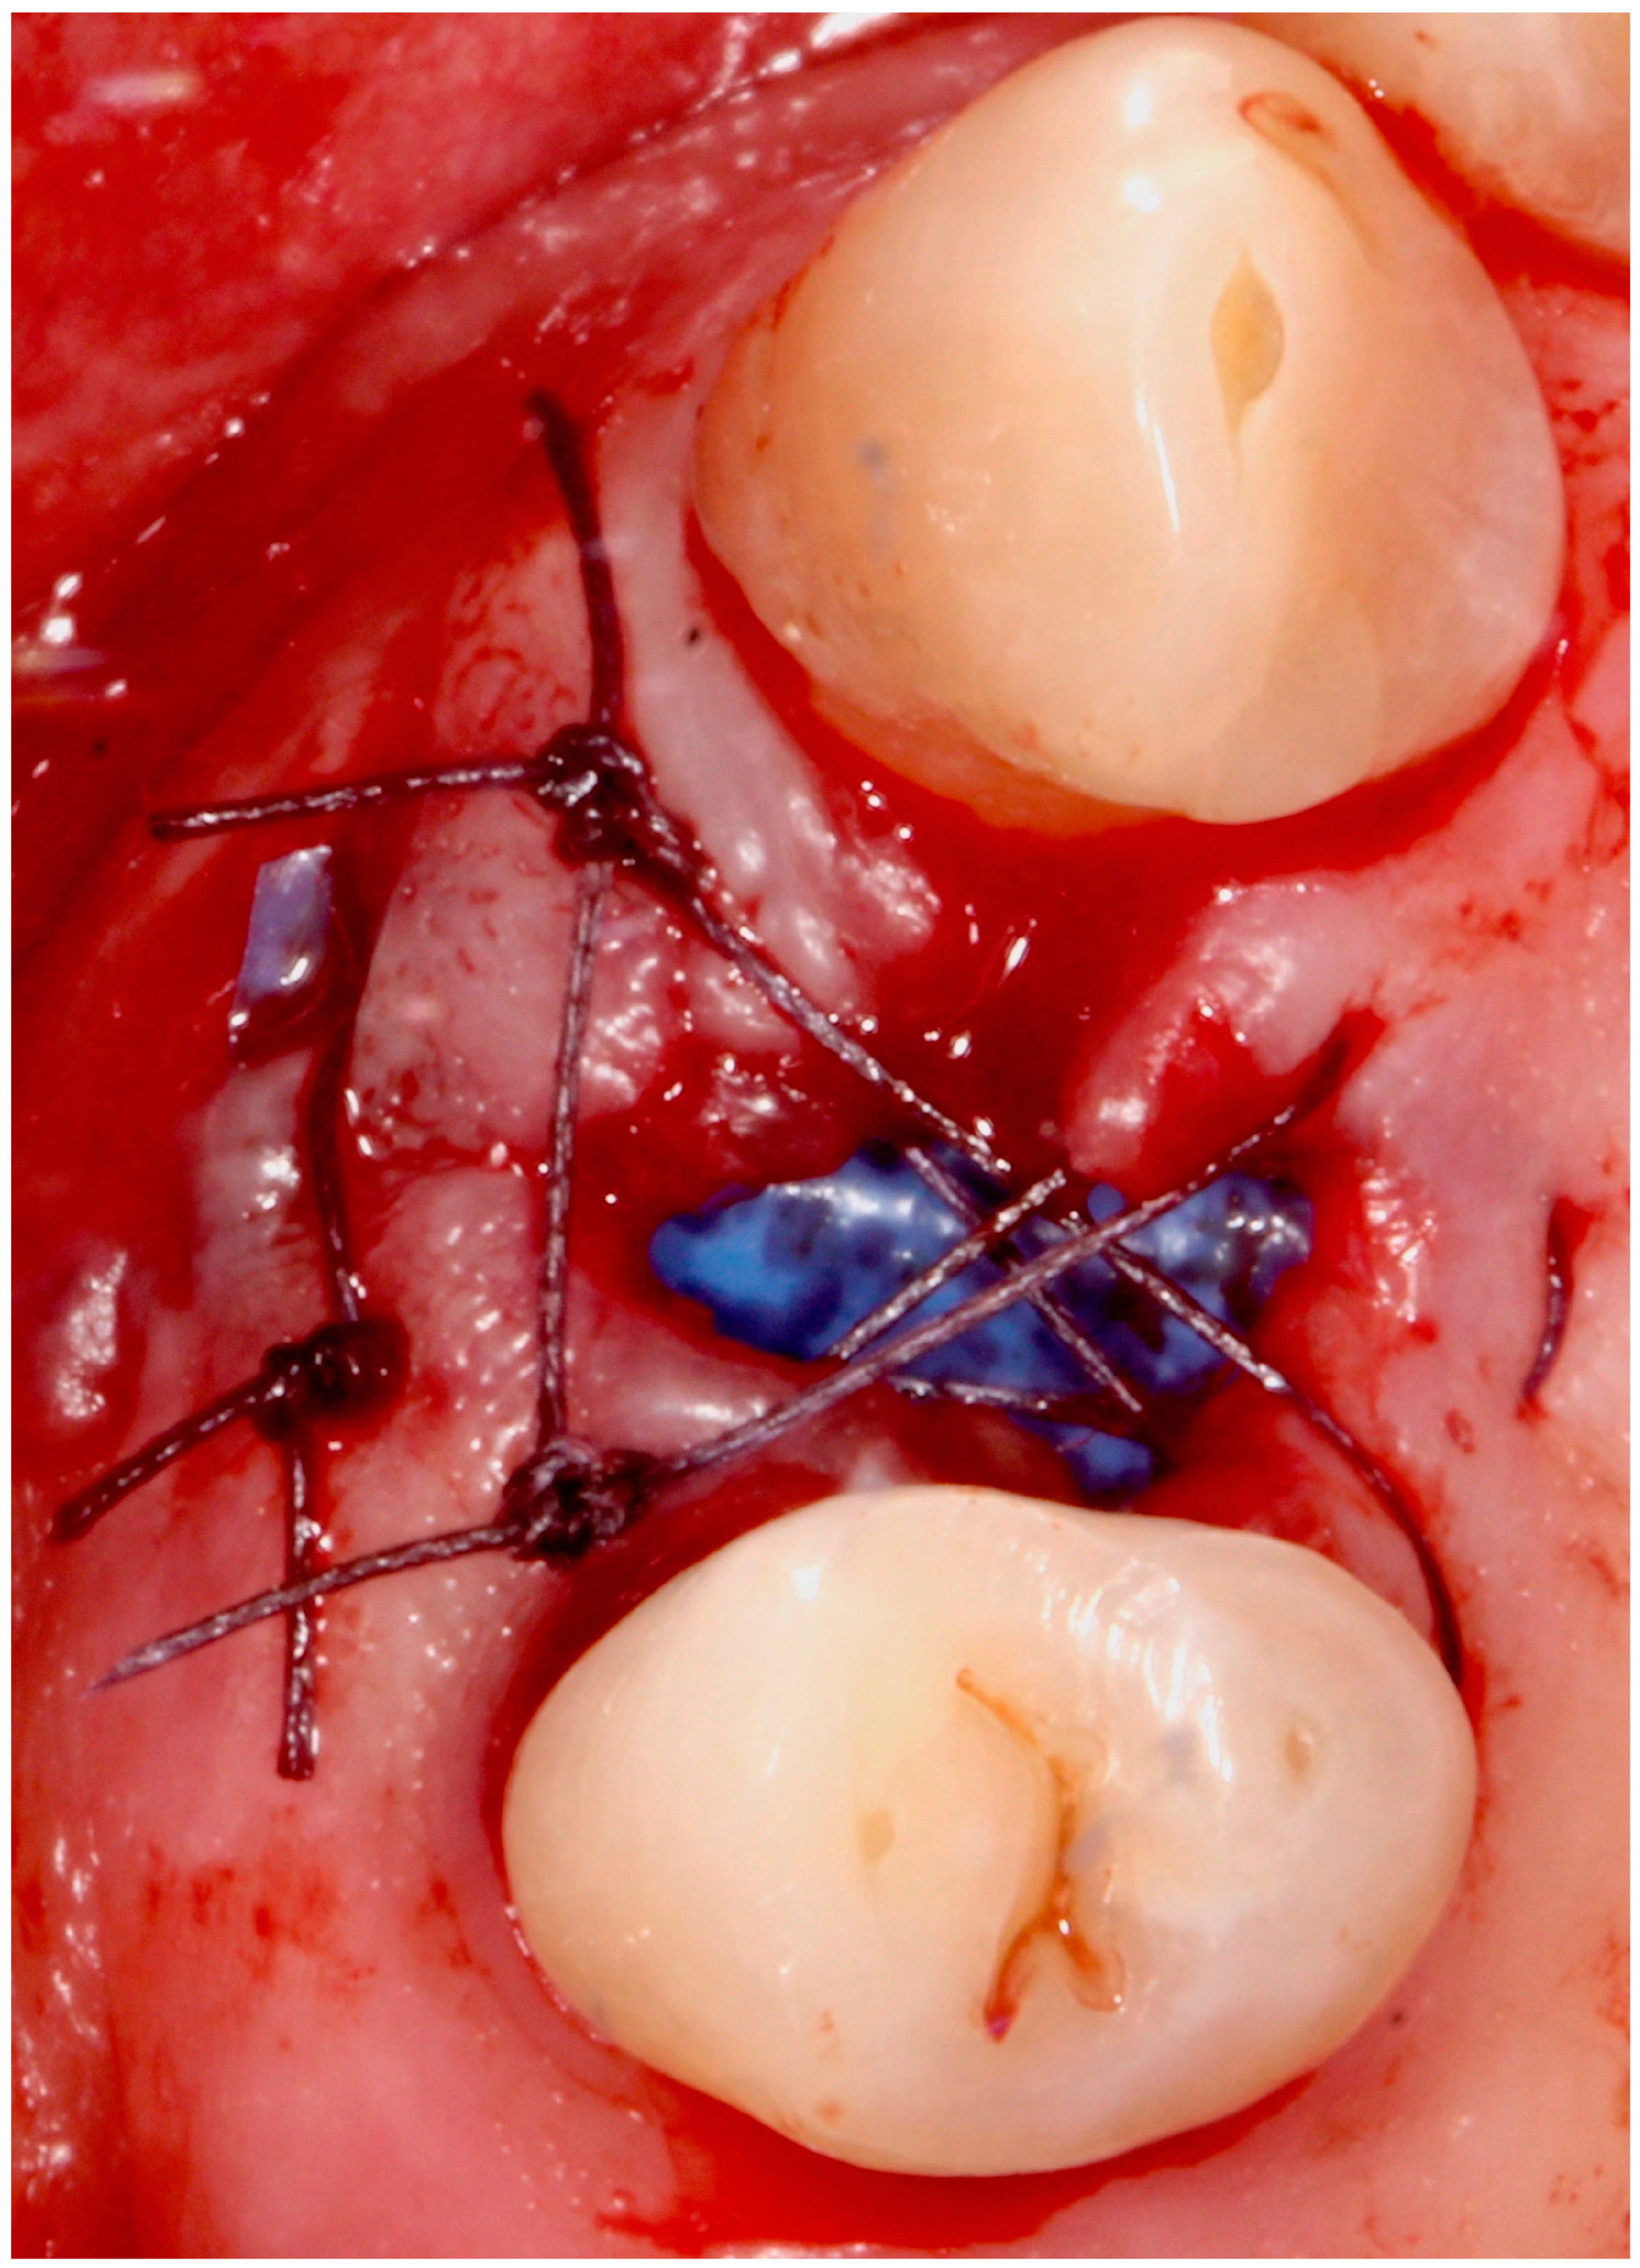

5.4. Surgical Technique